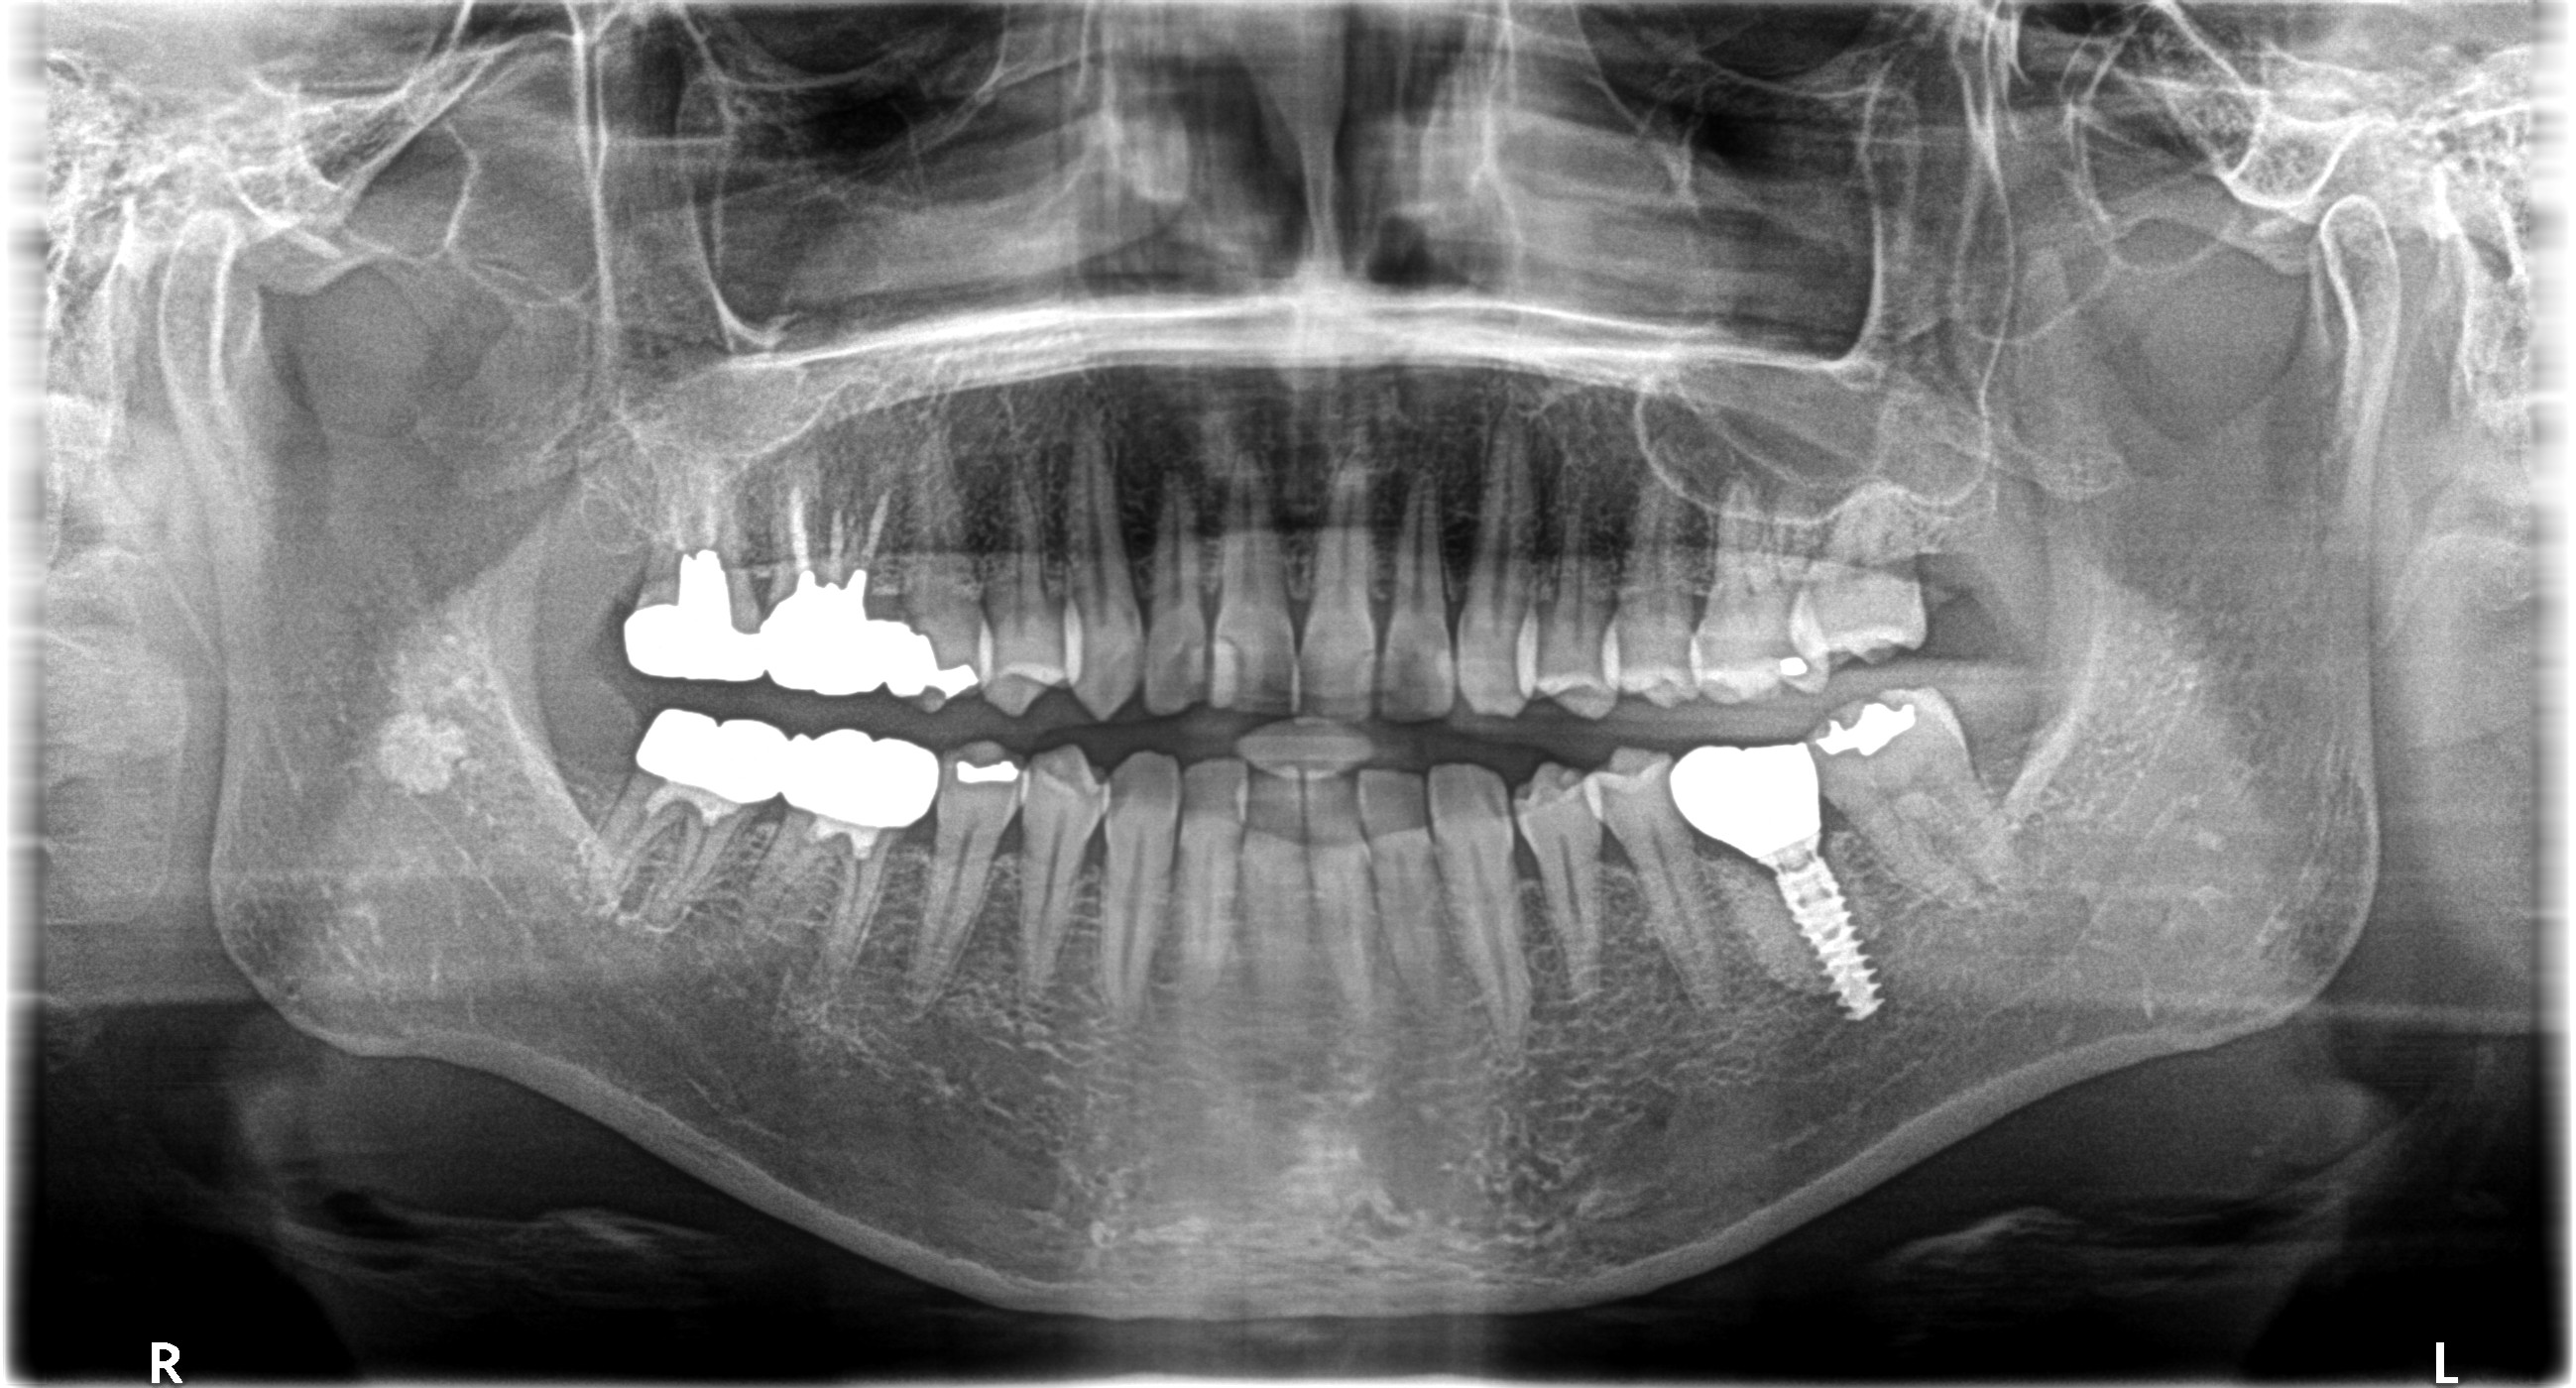

こちらが処置前のレントゲンです

左下第一大臼歯の保存が難しくImplant治療になりました

状態がそこまで悪くなかったのとこの患者さまは歯科治療が苦手でIVS(静脈内鎮静法)下にて抜歯と同時にGBR(骨造成)とImplant埋入まで行いました!

骨硬化とインテグレーションは1年以上待ち、しっかり固まったのを確認してから上部構造の殖立へと移行しました

処置後のレントゲンです👀

🦷治療内容:GBR(骨造成)・Implant(Nobel Biocare)

🦷担当医:Dr.小林

🦷麻酔科医:Dr.鈴木

🦷技工所:プロミネント